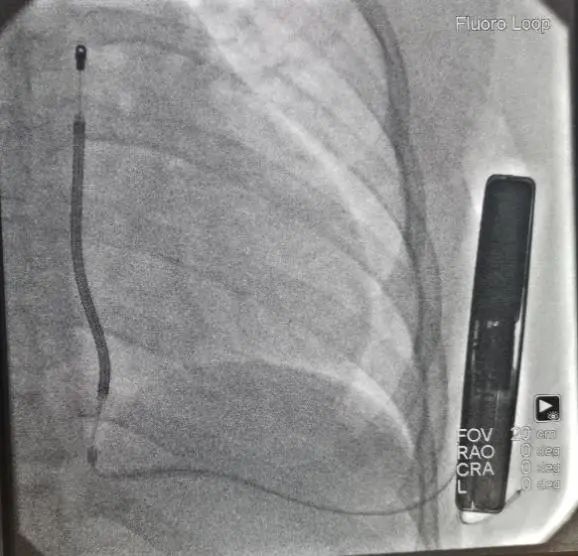

第一阶段手术

手术在全麻下进行,采用两切口植入技术。在经过X光片正位和左侧位确认后,标记能够获得最大心室除颤面积的导线和机壳所在位置并且划线,囊袋切口和剑突旁切口以及隧道,于囊袋切口切开皮肤6-7cm,逐层分离皮下组织至深筋膜层,制作前锯肌和背阔肌之间的肌间囊袋,保证足够的空间容纳装置并且装置位于肌间。按照标记的剑突旁切口切开皮肤3-4cm分离至筋膜层,通过皮下隧道导引针制作剑突至囊袋隧道,撤除导引针保留鞘管,将皮下除颤电极从鞘管穿出到剑突切口,撤除鞘管固定电极;再用另一个隧道针沿着既定路线制作胸骨上隧道,撤出隧道针,将皮下电极送入保留的鞘管,最后撕除鞘管。对所有伤口区进行有效止血,同时通过冲洗清洁所有切口,通过按摩将隧道内空气排出,避免因为空气残留导致的误放电。随后连接装置,置入囊袋内,逐层缝合皮下组织和皮肤,术区纱布覆盖,包扎,弹力绷带加压包扎止血。

术中行DFT测试, 65J一次除颤成功。